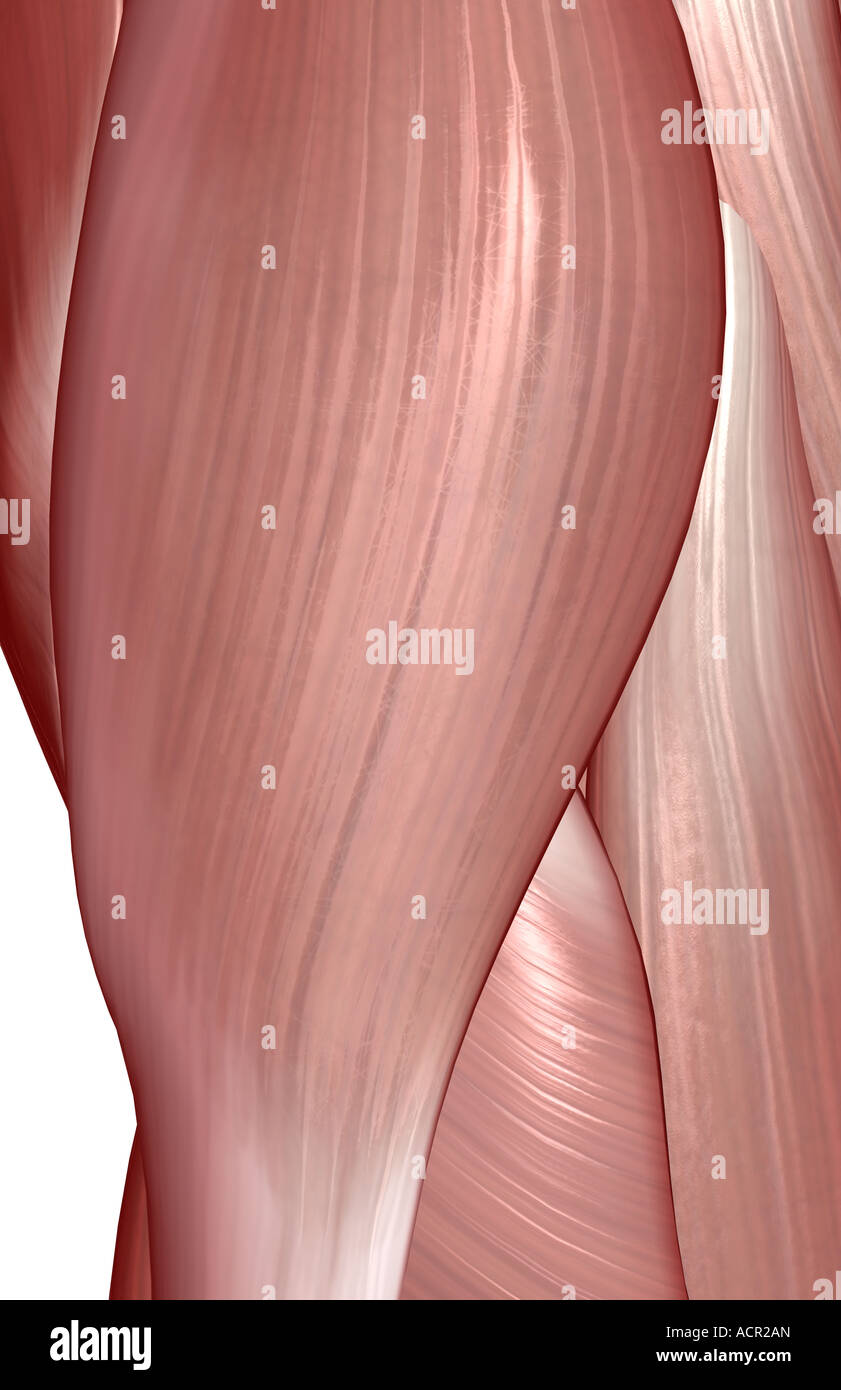

The muscles of the hip Stock Photohttps://www.alamy.com/image-license-details/?v=1https://www.alamy.com/stock-photo-the-muscles-of-the-hip-13212764.html

The muscles of the hip Stock Photohttps://www.alamy.com/image-license-details/?v=1https://www.alamy.com/stock-photo-the-muscles-of-the-hip-13212764.htmlRFACR2AN–The muscles of the hip